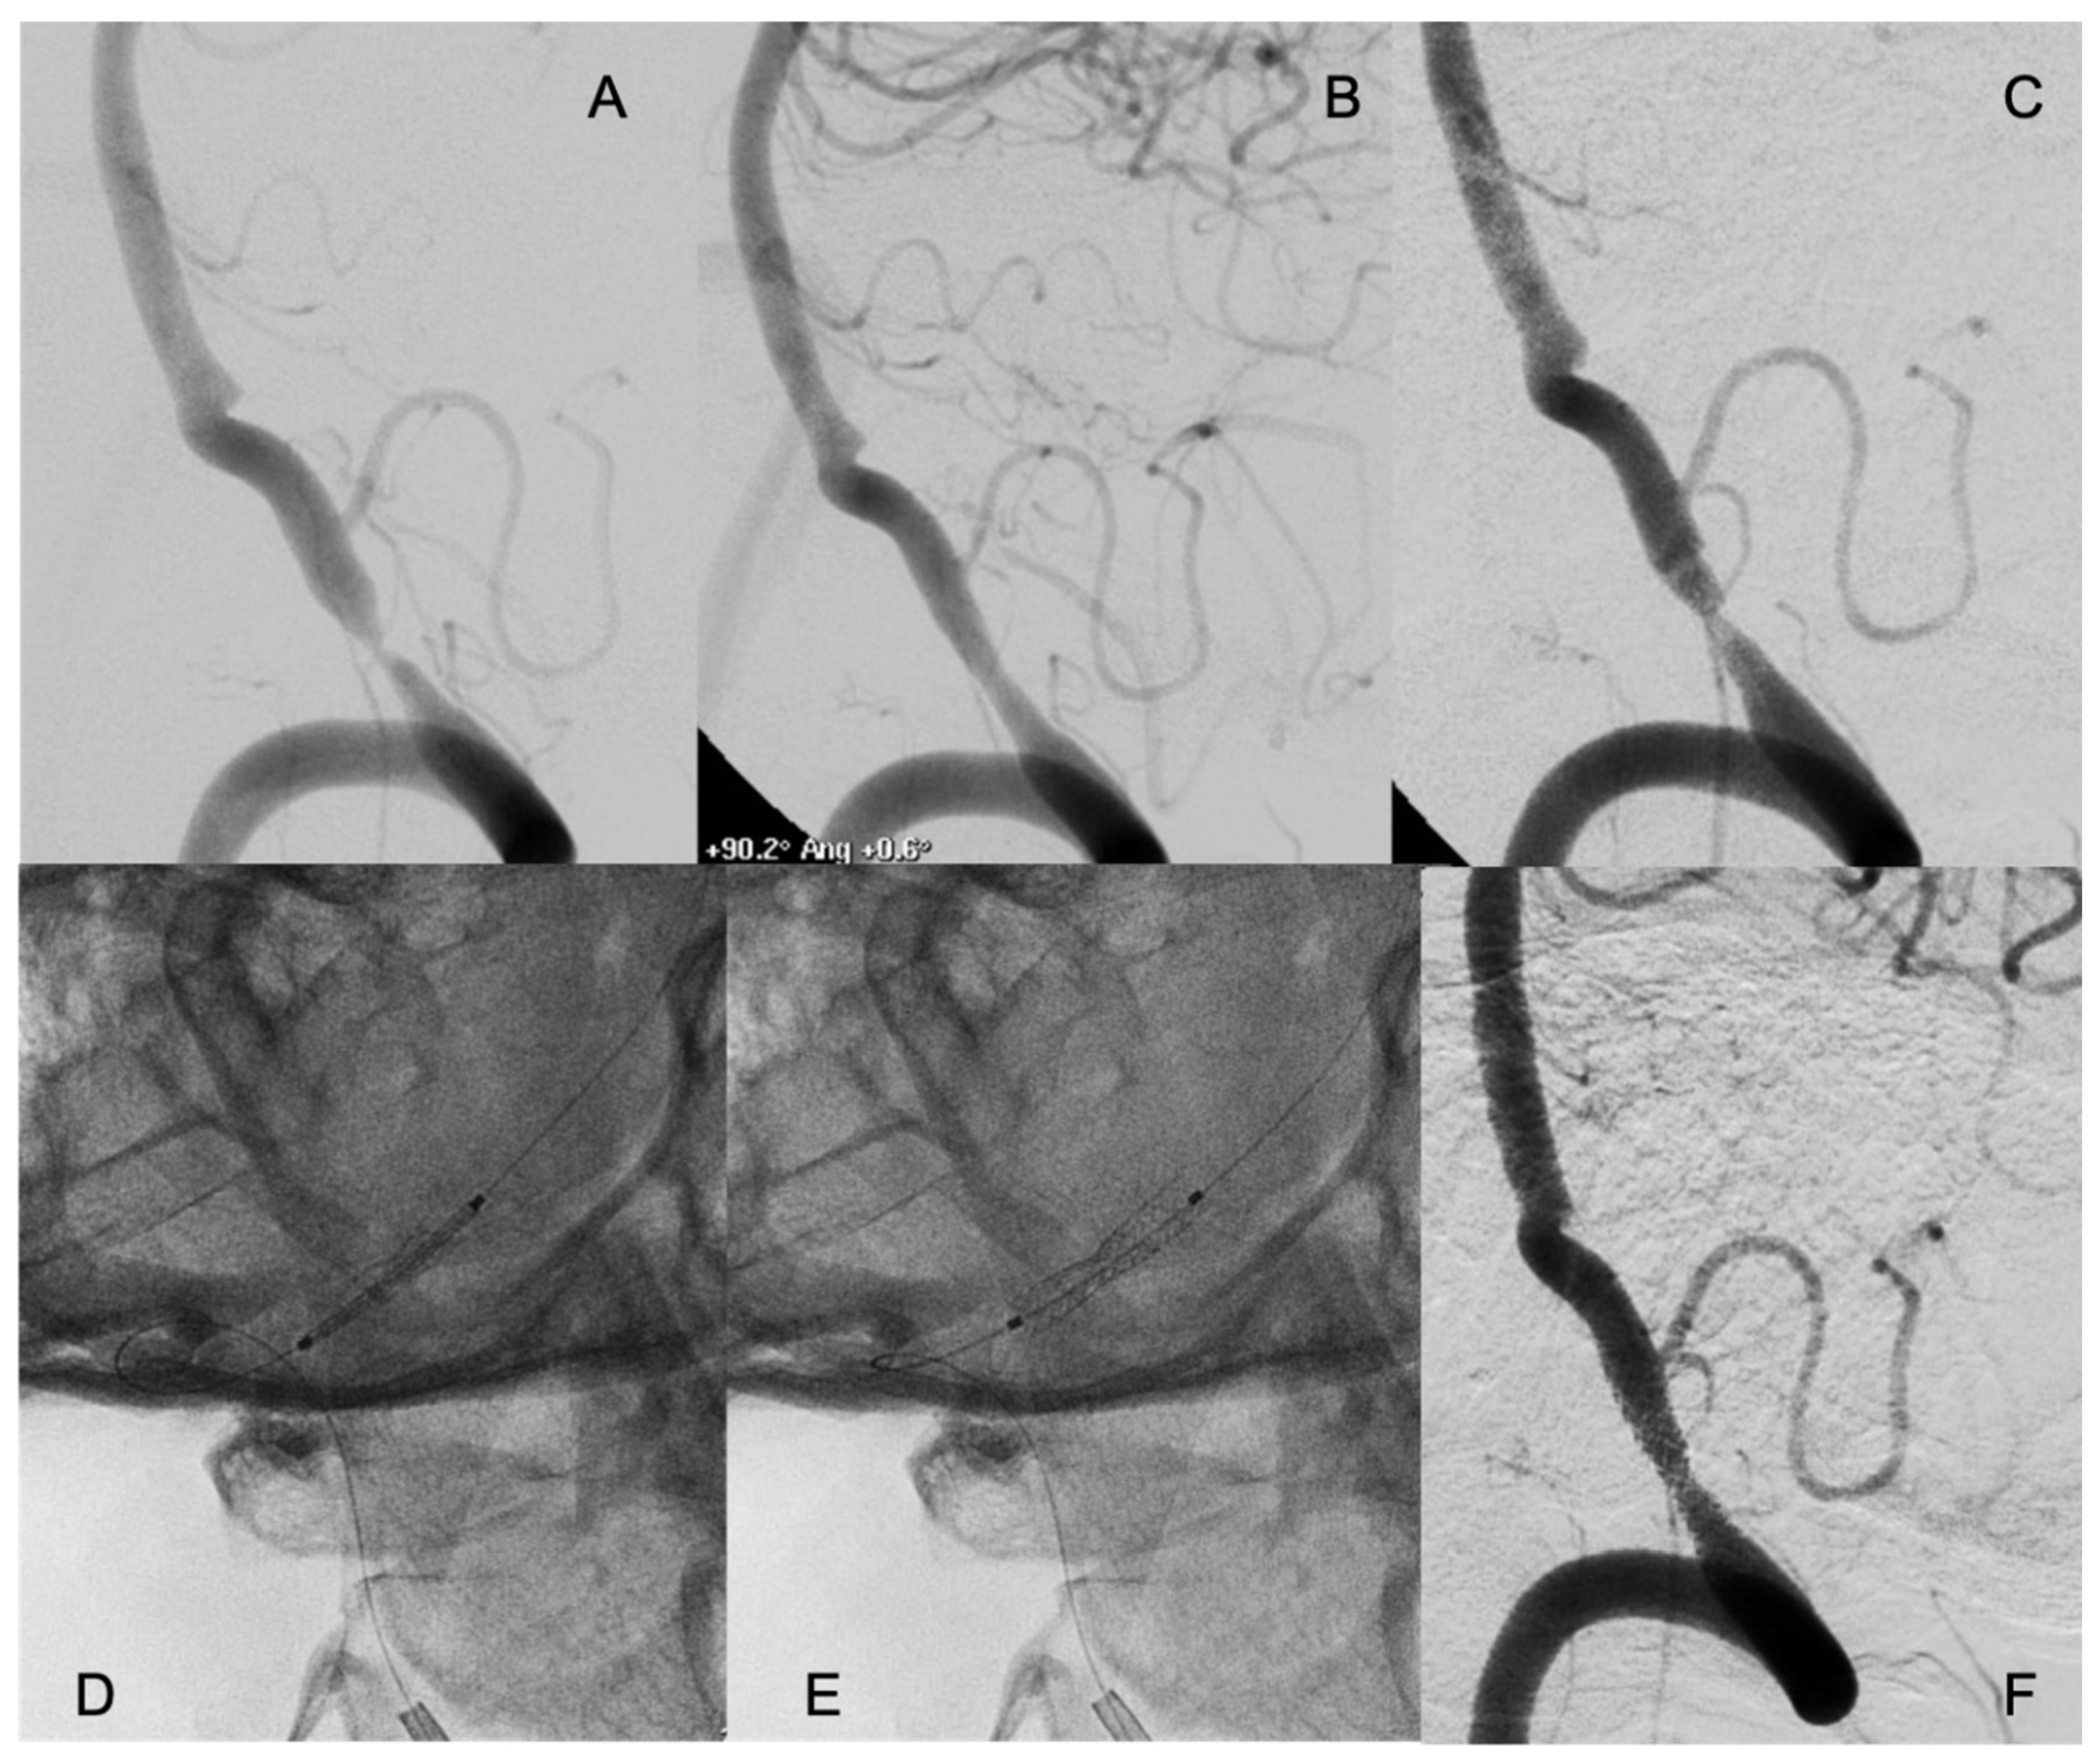

3.2. Procedure Characteristics